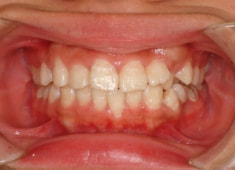

治療前

治療後(1年12ヶ月後)